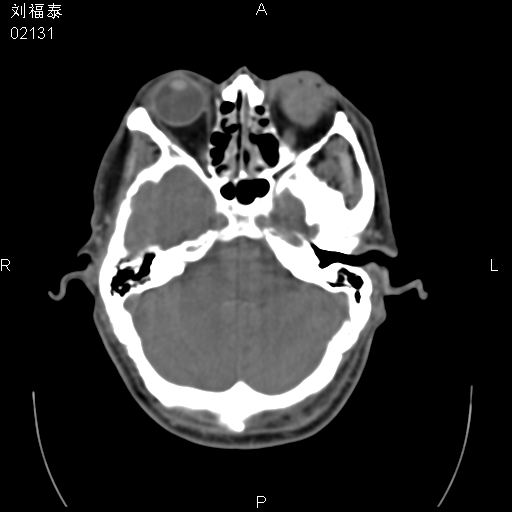

以下是引用余辉在2008-3-4 14:00:00的发言:[br]考虑左眼球黑色素瘤或血管源性肿瘤可能性大,建议增强检查

以下是引用余辉在2008-3-4 14:00:00的发言:[br]考虑眼球黑色素瘤或血管源性肿瘤可能性大,建议增强检查

以下是引用zsl6918在2008-3-4 15:08:00的发言:[br]现有征象只能提示球内出血,视网膜脱落,至于是否为肿瘤性病变需mri检查。